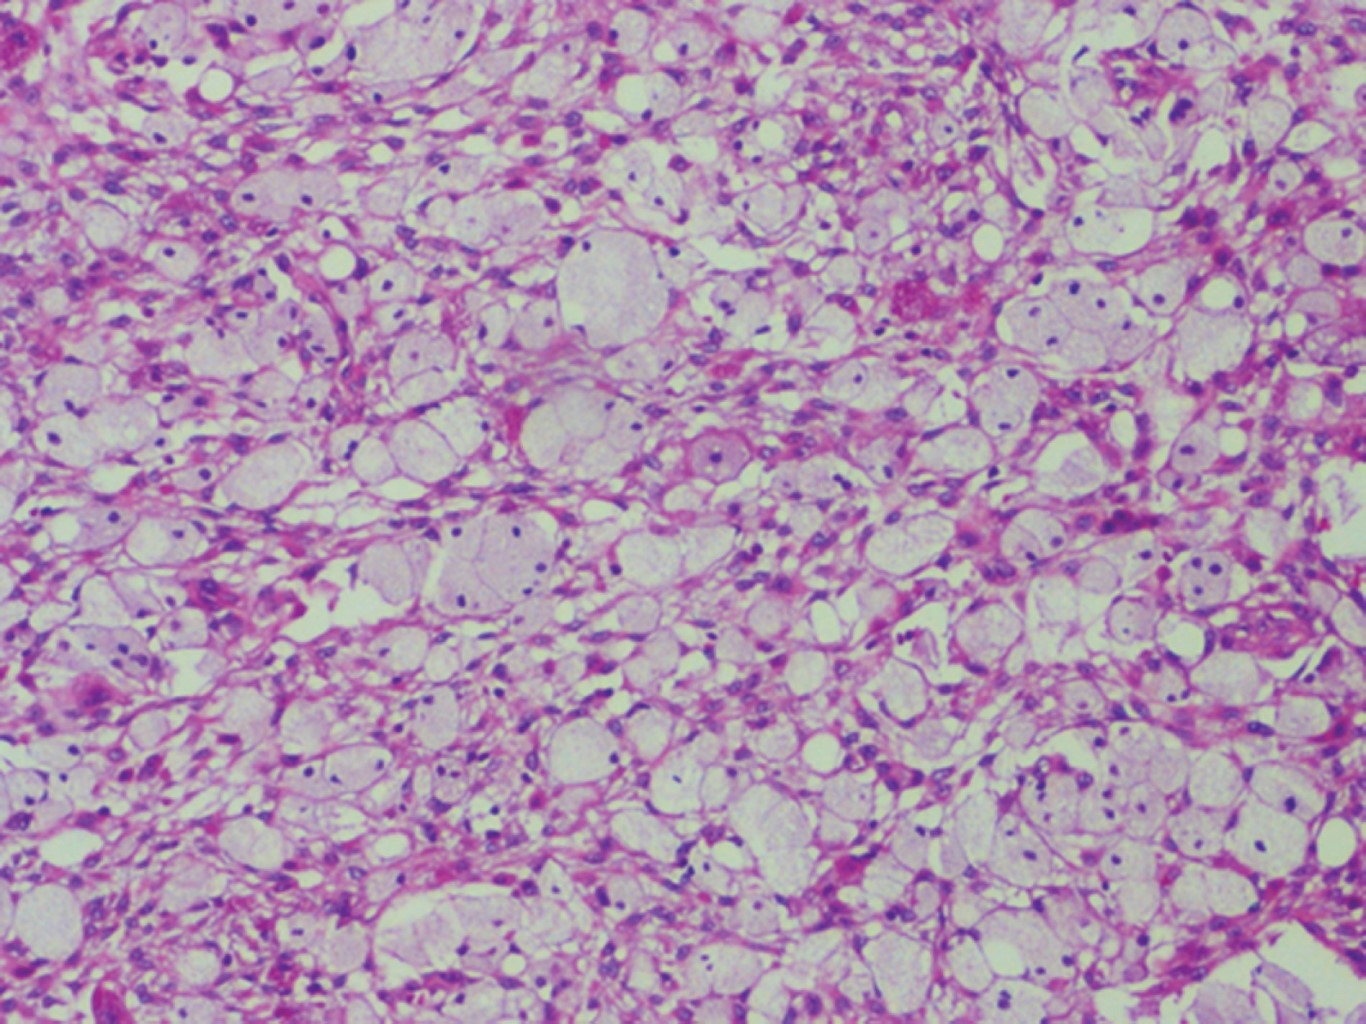

Histopatológicamente, se aprecian células histiocíticas y macrófagos con contenido lipídico o células espumosas en un citoplasma granular, de manera ocasional se observan células gigantes multinucleadas en un estroma de tejido conectivo fibroso, también pueden detectarse de manera ocasional cristales de colesterol dentro de la lesión.4,11

El espécimen está constituido por células xánticas dispuestas en grupos así como células histiocíticas dispuestas en remolinos en un estroma de tejido conectivo fibroso bien vascularizado, con presencia de infiltrado inflamatorio crónico (Figura 4).

Figura 4